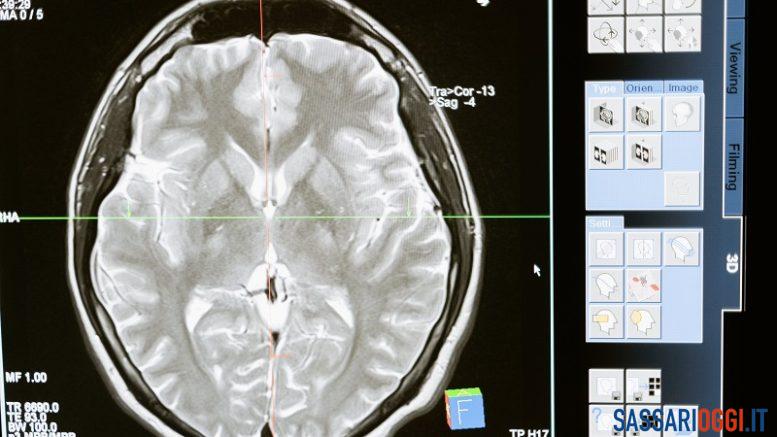

In Sardegna sono circa 12mila le persone affette da epilessia e oltre 6mila sono i pazienti che ne soffrono in età evolutiva. L’epilessia è una malattia neurologica tra le più comuni in età evolutiva e con diversi gradi di gravità, che possono essere imputabili a differenti eziologie, genetiche, strutturali, metaboliche, spesso multifattoriali.

Ma oltre a essere caratterizzate da crisi ricorrenti, le epilessie, quelle più gravi e resistenti ai farmaci, secondo gli esperti possono essere associate anche a disturbi nei vari ambiti dello sviluppo neuro-cognitivo del paziente in età evolutiva come, per esempio, disturbi del comportamento, disturbi negli apprendimenti, nella attenzione, nel funzionamento cognitivo e sociale con ripercussioni nell’autostima e nelle relazioni interpersonali.